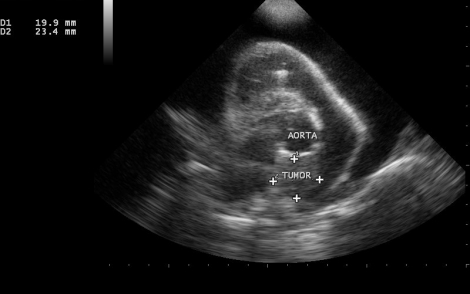

Tiriant miokardą, ties aortos pagrindu buvo aptikta dažniausiai pasitaikanti skysčio kaupimosi perikarde priežastis didesnių veislių vyresnio amžiaus šunims – 2x3 cm dydžio navikas (žr. nuotrauką).